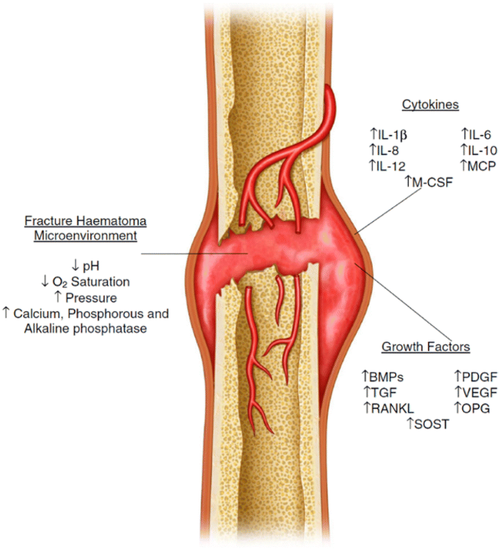

Bone healing after surgery can be complex, and one of the most serious complications is non-union, where the bone fails to properly heal. This is especially a concern in procedures like limb lengthening, where the body is required to generate significant new bone. When healing does not occur correctly, it can lead to poor outcomes and may require additional surgeries.

One area of interest in improving bone healing is Low-Intensity Pulsed Ultrasound (LIPUS). Research has shown that LIPUS can stimulate periosteal apposition, which is the formation of new bone along the outer surface of existing bone. This process is important not only for healing but also for changing the thickness and shape of bones.

Periosteal apposition plays a key role in how bones grow outward. Unlike lengthwise growth, which mainly happens during development, this type of growth affects the external structure of the bone. Because of this, it is relevant when considering changes in bone appearance or structure.